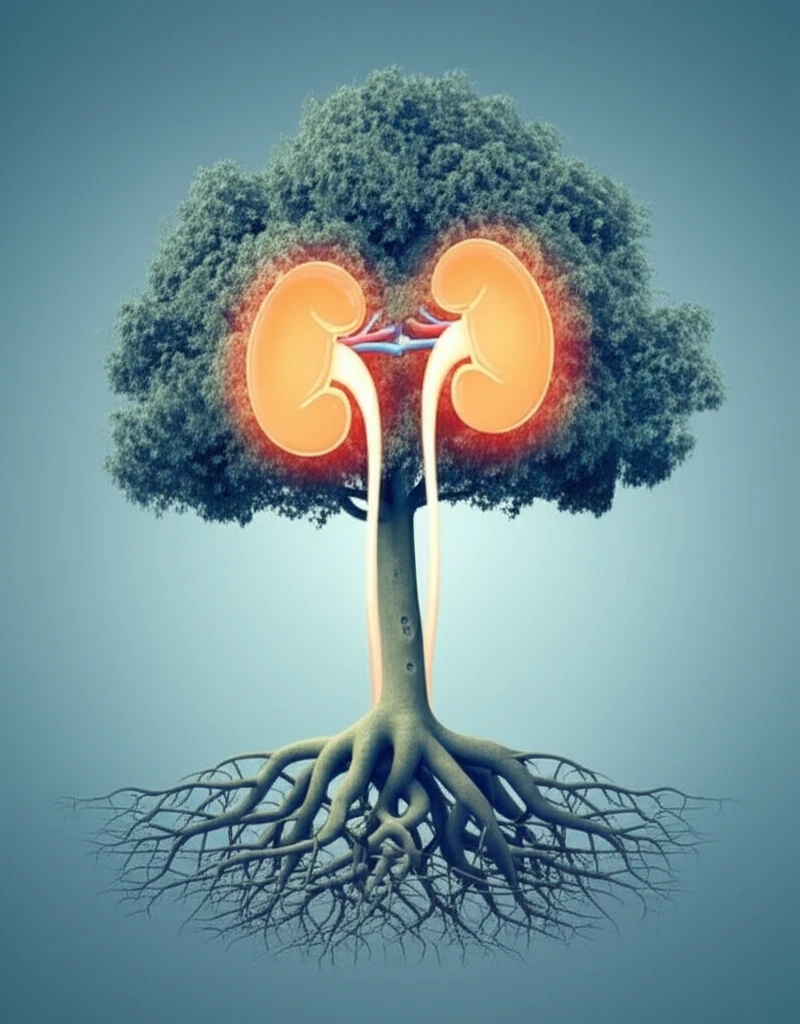

Open aortic surgery (OAS) is a major procedure, but sometimes it's the best option for treating serious aortic conditions. If you're facing this surgery, understanding the potential complications is crucial for a smoother recovery. One of the main concerns is the possibility of renal (kidney) issues arising after the procedure, especially when the surgery involves clamping the aorta above the renal arteries.

When surgeons perform OAS requiring SRACC, they temporarily clamp the aorta to control blood flow. While this is necessary to perform the surgery, it can temporarily reduce blood flow to the kidneys. This reduced blood flow can lead to a condition called postoperative renal insufficiency (PORI), where the kidneys don't function as efficiently as they should after the surgery.